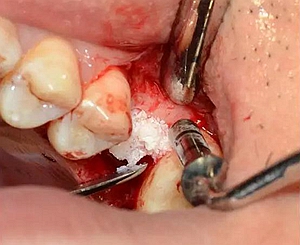

逐次添加少量骨粉,加壓到位,反復(fù)進(jìn)行。骨粉總量約0.25g